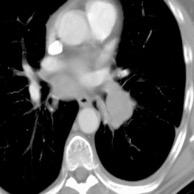

Signos radiológicos TC

Hallifax RJ et al. State-of-the-art: Radiological investigation of pleural disease Respiratory Medicine 2017

Nivel hidroaéreo o burbujas

Forma lenticular o elíptica Ángulos obtusos

> Grasa Extrapleural (60-80%)

Situación no gravitacional (no siempre)

Compresión de estructuras pulmonares

Límite muy bien definido Tabicación

Patrón ecográfico de empiema

Empiema

El derrame paraneumónico se convierte en complicado en 5-10% de los casos